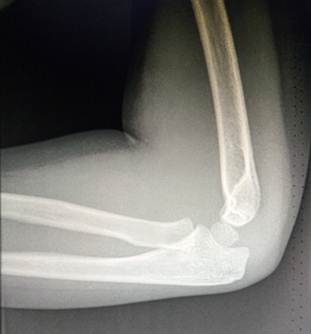

11- 13 лет

Это возраст, в котором все ядра окостенения достигли максимального

развития и приняли формы соответсвующих образований. На рентгенограммах их

разделяют узкие полоски ростковых зон. Это максимальный расцвет детского локтя.

Возраст

12 лет. Все ядра окостенения локтя развиты и разделены узкими хрящевыми

прослойками. Вершина локтевого отростка содержит основное ядро окостенения и

ядро – спутник неправильной формы.

14 лет. Стремительное закрытие зон роста локтевого сустава. Можно заметить

узкие просветы в основании медиального и латерального надмыщелков, а также пока

еще открытую зону роста в локтевом отростке.